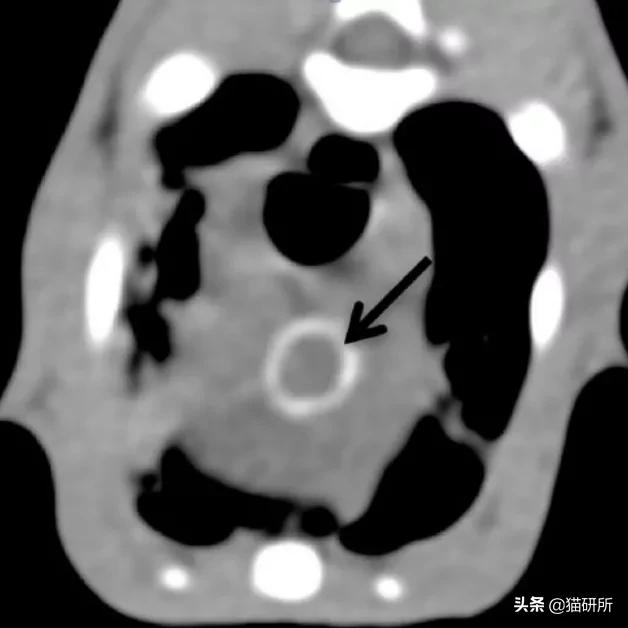

4个月大的家养短毛猫,咳嗽、干呕。

疱疹病毒等检测隐形,抗生素治疗不敏感,血液检查发现高钙血症,CT显示主动脉弓、主动脉根部矿化,肺部表现与矿化、纤维化或炎症表现一致。

经详细病史排查及第三方机构检测,发现主人饲喂的罐装零食存在维生素过量,诊断为高维生素D中毒。